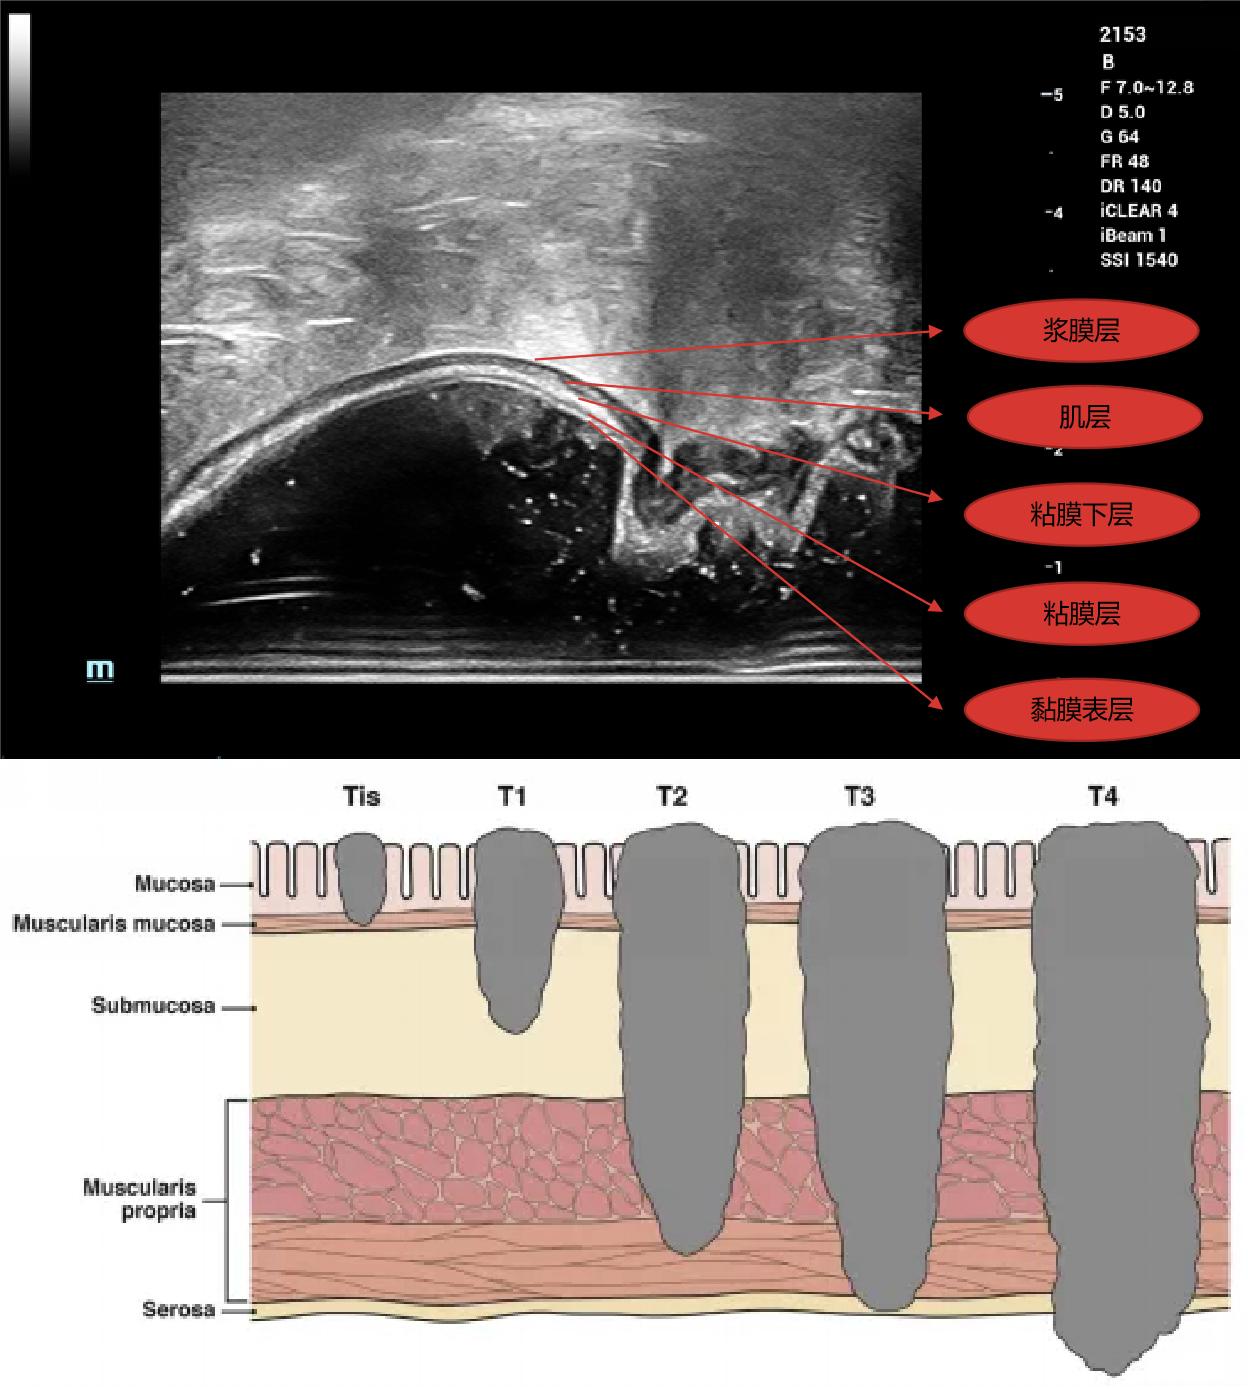

3、双平面探头最高频率12.8Mhz,能显示出直肠壁5层结构